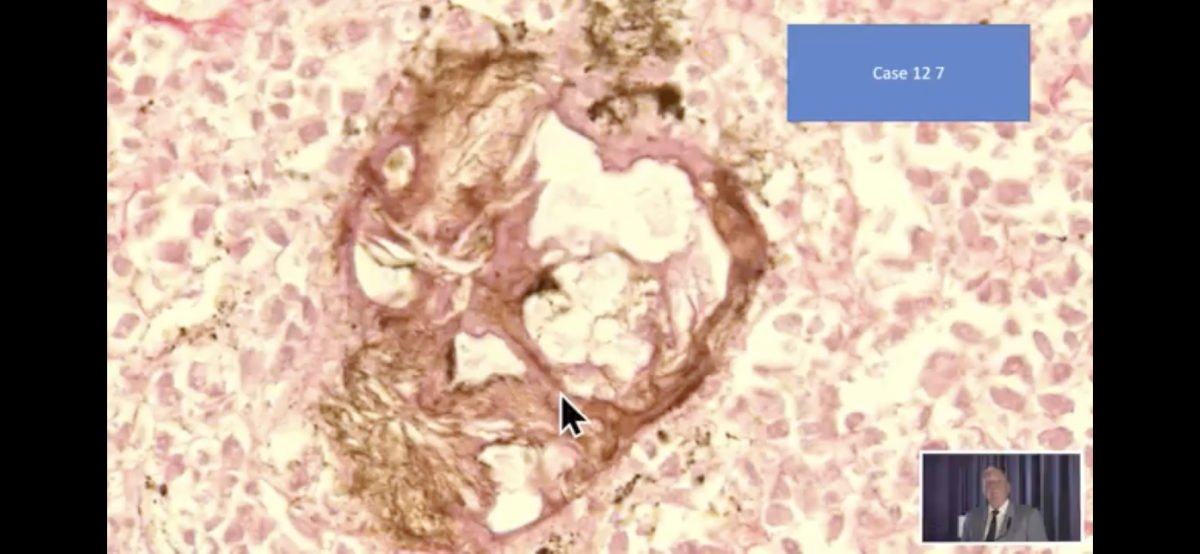

Video 9.10.2021: Pfizer

vaccine=toxic agent! -

Pfizer-Impfstoff=Kampfstoff! Objekte+Fäden

(25''): https://www.bitchute.com/video/YqnKldt4iyOH/

Pfizer-Impfstoff=Kampfstoff! (25'')

Link: https://www.bitchute.com/video/YqnKldt4iyOH/

- Bitchute-Kanal: NatMed-etc. - hochgeladen am

10.10.2021